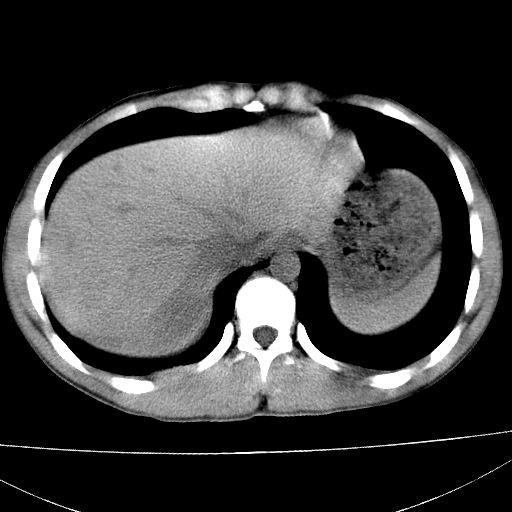

标题: CT15860:男,21岁,腹部外伤2小时伴胸疼。 [打印本页]

标题: CT15860:男,21岁,腹部外伤2小时伴胸疼。

b超示:肝破裂。

肝脏及肾脏明显有损伤性改变并激发腹腔内积液(血),以肝脏撕裂及肾周积血显著。

1)肝破裂伴腹腔积液(血)。2)右肾破裂伴右肾包膜下及肾周血肿。3)腹部空腔脏器穿孔可能。4)右侧少量胸腔积液(血)。

1)肝破裂伴腹腔积液(血)。2)右肾破裂伴右肾包膜下及肾周血肿。3)右侧少量胸腔积液(血)。

肝肾挫裂伤,右肾周及包膜下血肿,腹腔积液

肝、右肾包膜下血肿,右侧腰大肌及腹膜后血肿;腹腔少量积血;腹腔疑有少量游离气体伴肠破裂。

肝右叶及右肾均见挫伤破裂出血。